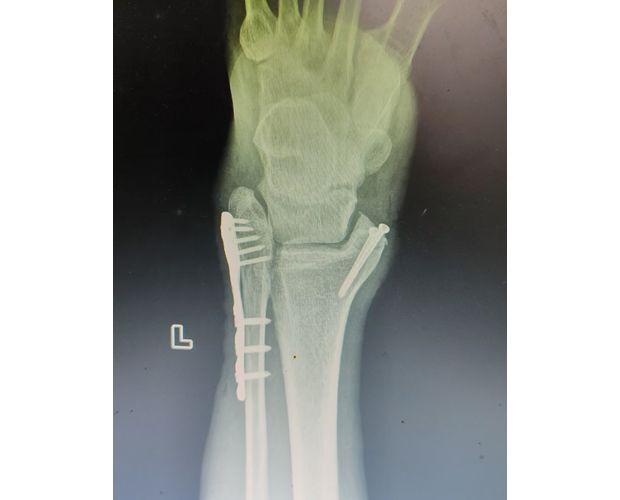

2月4日,何店鎮(zhèn)中心衛(wèi)生院接診一名左踝關(guān)節(jié)外傷患者,經(jīng)影像檢查,確診為左脛、腓骨下段骨折。外科醫(yī)生姜穩(wěn)迅速完成術(shù)前檢查及病情評(píng)估,并與患者及家屬深入溝通治療方案。在患者強(qiáng)烈要求于本院進(jìn)行手術(shù)的情況下,為最大限度保障手術(shù)質(zhì)量與安全,該院特邀請醫(yī)共體牽頭單位——曾都區(qū)人民醫(yī)院脊柱創(chuàng)傷外科專家團(tuán)隊(duì)前來指導(dǎo)。

本次幫扶由曾都區(qū)人民醫(yī)院脊柱創(chuàng)傷神經(jīng)外科主任徐三軍帶隊(duì),專家團(tuán)隊(duì)抵達(dá)后立即完成手術(shù)風(fēng)險(xiǎn)評(píng)估及術(shù)前準(zhǔn)備。手術(shù)過程中,徐三軍主任嚴(yán)格規(guī)范完成各項(xiàng)手術(shù)操作,并同步結(jié)合手術(shù)步驟,為該院外科醫(yī)師詳細(xì)講解骨折手術(shù)的關(guān)鍵要點(diǎn)、操作技巧、術(shù)中注意事項(xiàng)及術(shù)后康復(fù)要領(lǐng)。通過“手把手”的實(shí)戰(zhàn)帶教,專家將豐富的手術(shù)經(jīng)驗(yàn)與規(guī)范的診療思路傾囊相授,讓該院醫(yī)護(hù)人員在實(shí)操中學(xué)習(xí),在過程中成長。